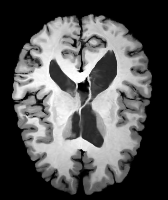

Results: All trained networks are evaluated using Dice overlap scores between predictions and the manual segmentations for the segmentation network, or between the warped moving segmentations and the target segmentations for the registration network. Tabs. 1 and 2 show results for the knee and brain MRI experiments respectively in Dice scores (%). Fig. 2 shows examples of knee MRI registrations and brain MRI segmentations.

Qualitative results: DA achieves more anatomically consistent registrations than the mono-networks on the knee (Fig. 2) and Brain MRI samples (see supplementary material).

Moving

Target

Mono-0

Mono-21

DA-1

DA-21

Mono-65

Image

Manual Seg

DA-1

Mono-5

DA-5

Mono-200